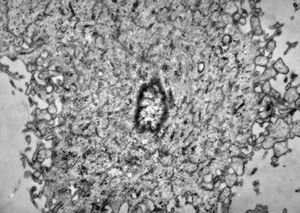

M,50y. | Pneumocystis carinii - lung